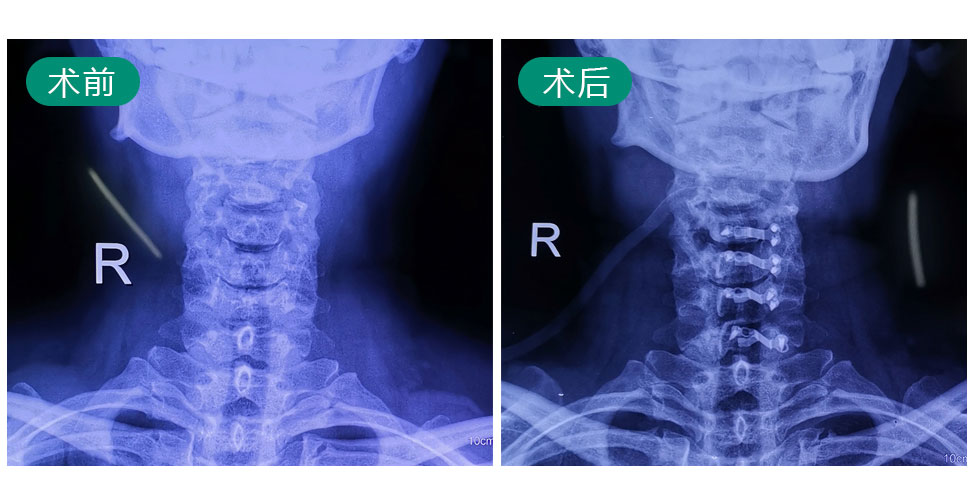

姓名:钟某某   性别:女   年龄:47岁

症状:颈部伴右肩疼痛4年,病情加重半月

使用单边双通道内镜技术治疗,现已康复